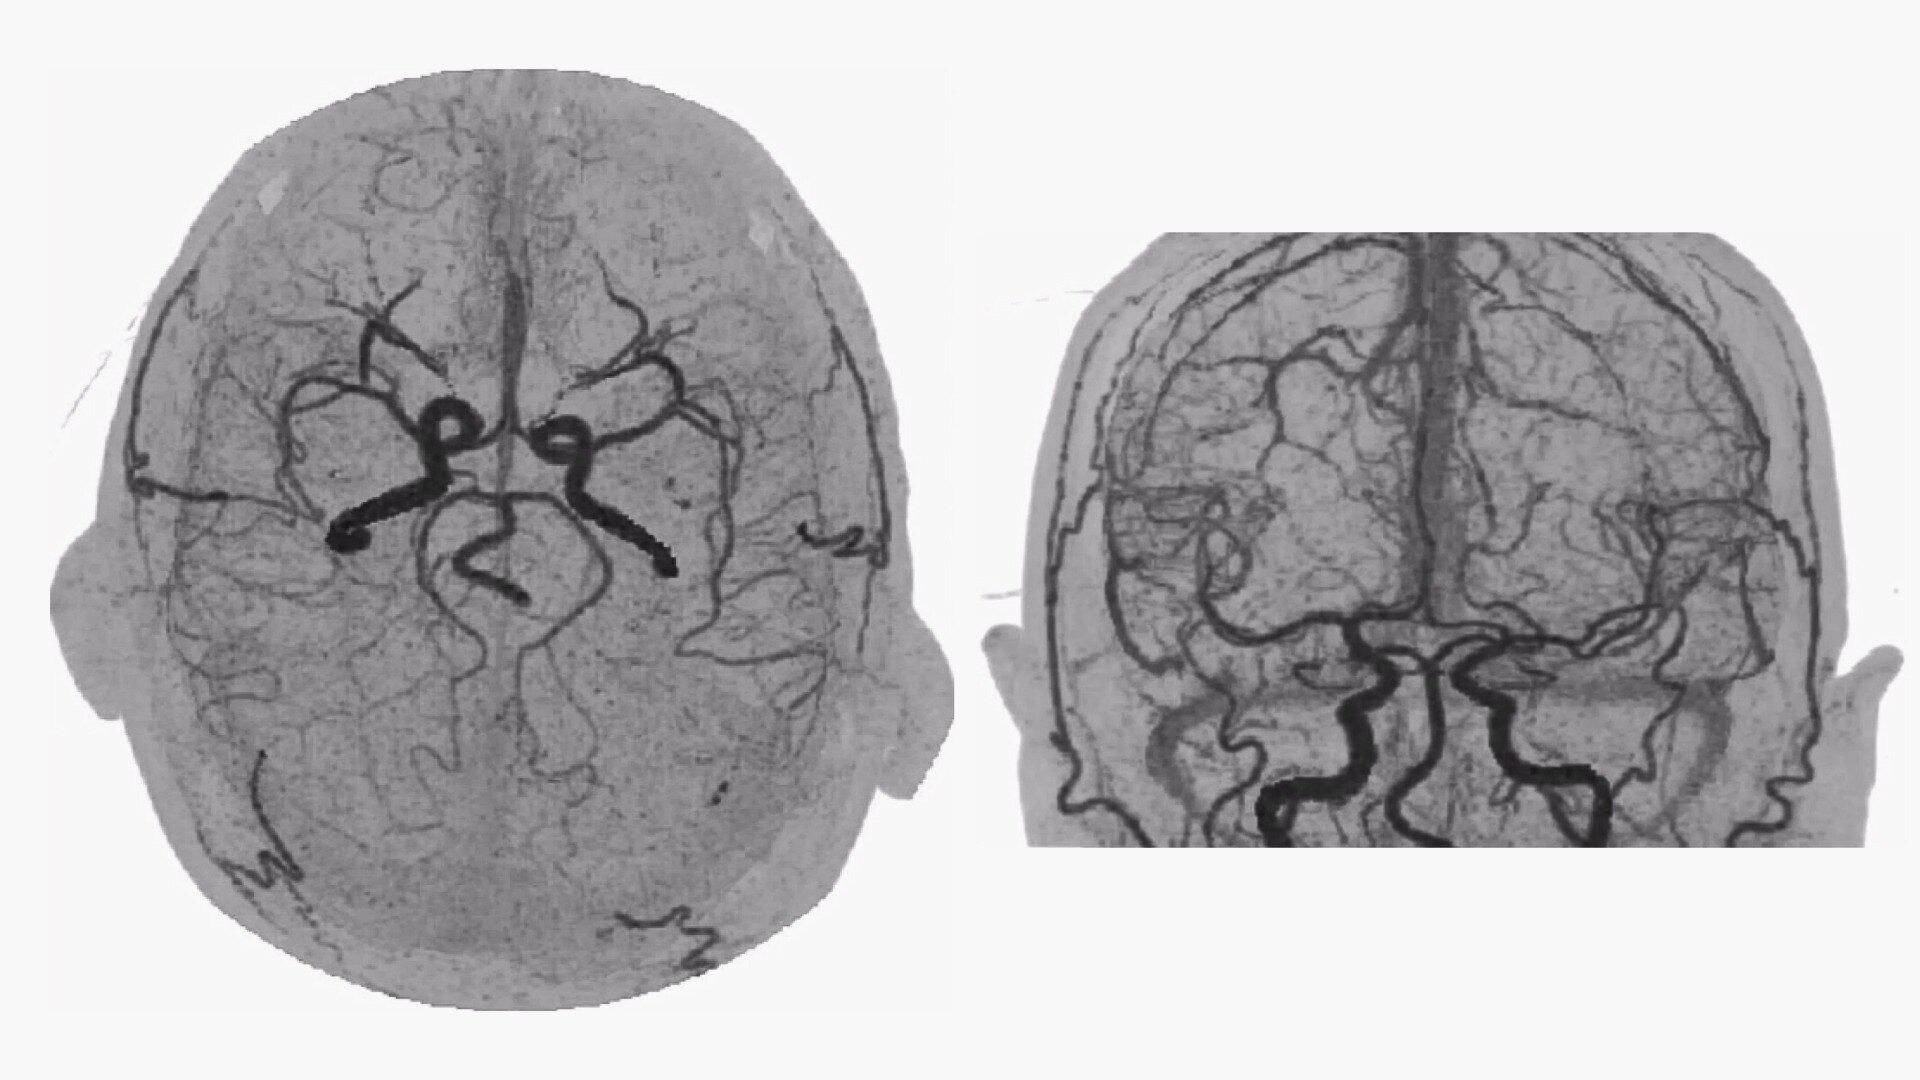

Bone-free dynamic visualization of vascular anatomy.

• 4D Neuro Digital Subtraction angiography (DSA) automatically performs image registration, then removes bone.